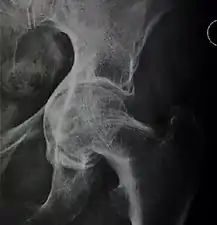

X-ray of the hips of a 40-year-old female, with dysplasia of her right hip.

In the adult hip there are important landmarks to be recognized on plain film radiographs:[3]